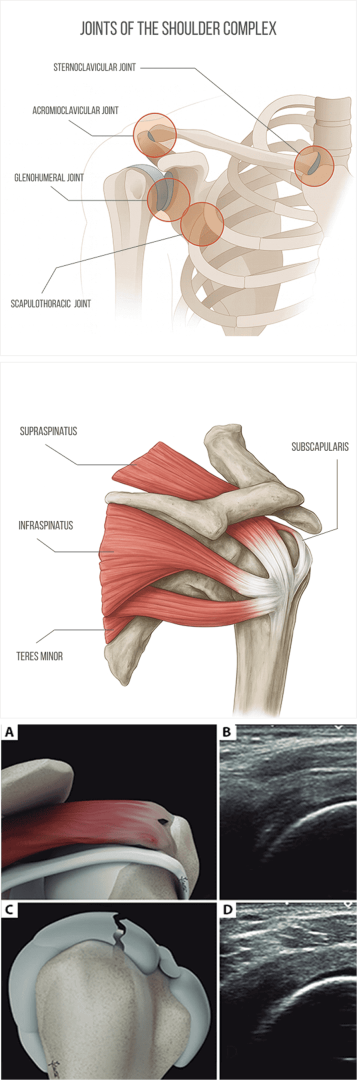

Shoulder anatomy and common causes of shoulder pain

The shoulder complex encompasses more than just the glenohumeral joint – it involves multiple joints, muscles, fascia, ligaments, and other tissues that work together to produce, guide, and control movement. Its complex architecture makes the shoulder the most mobile joint in the human body, but its mobility comes at the cost of stability, making it prone to injury.

Joints of the shoulder complex:

• The glenohumeral joint forms the ball-and-socket architecture that gives the shoulder its broad range of motion.

• The acromioclavicular joint connects the acromion of the scapula to the clavicle, allowing for limited gliding.

• The sternoclavicular joint attaches the clavicle to the sternum, allowing for elevation, depression, protraction, retraction, and some rotation of the shoulder girdle.

• The scapulothoracic articulation, although not a true joint, allows the scapula to glide over the posterior thoracic wall, enabling it to tilt, rotate, and slide.

The glenohumeral joint’s shallow socket makes it vulnerable to dislocations and subluxations, especially when stabilizing structures are weak, damaged or imbalanced. Stability is provided by the rotator cuff muscles and tendons, the labrum of the glenoid, and ligaments. Fascia also plays a critical role in protecting the shoulder during physical activity, helping to guide and distribute forces via a network of elastic tension.

The rotator cuff is made up of four muscles and their tendons that compress the humeral head into the glenoid fossa, keeping it in place during movement. The infraspinatus, teres minor, subscapularis help to initiate and control shoulder rotation, while the supraspinatus aids in shoulder abduction. The rotator cuff works in concert with the deltoid, trapezius, and pectoralis major to produce smooth, coordinated motion.

Scapular stability is also important for optimal shoulder function. The scapular stabilizer muscles like the serratus anterior and trapezius hold the scapulae in position during movement, to prevent issues like winging or impingement. Multiple bursae provide shock absorption and reduce friction between tissues and bony structures. They also facilitate smooth gliding of the rotator cuff tendons beneath the acromion during arm elevation.